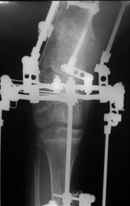

Деформация правой нижней конечности с 6 месяцев (стала прогрессировать после года, с момента начала ходьбы). Поставлен диагноз болезнь Олье, варусная деформация, укорочение правой нижней конечности на 4,5 см. 1993 г. - операция остеоклазия на уровне очагов поражения в н/3 правой бедренной кости и в/3 правой большеберцовой кости с одномоментной коррекцией деформации и фиксацией костных фрагментов спицами Киршнера.После начала статической нагрузки (1994 г.) появился рецидив деформации и укорочения. Вторая операция - ЧКО АВФ, аппарат демонтирован через 2недели в связи с развившимся на уровне стержня переломом, после чего находилась в гипсовой повязке до консолидации костных фрагментов. Далеелечилась консервативно в гипсовой повязке. Выраженная деформация и укорочение правой нижней конечности. Относительная длина бедер: справа -34 см, слева - 51 см; анатомическая длина голеней: справа - 29 см, слева - 39 см. Величина варусной деформации на уровне дистального отдела правого бедра составляет - 80 град. Амплитуда движений в коленных суставах (разгибание/сгибание ): справа - 0/0/100 град.; слева - 0/0/30 град. Отмечается боковая и ротационная нестабильность на уровне правого коленного сустава. Амплитуда движений в голеностопных суставах - в норме. Тактика лечения? Заранее благодарю! С уважением,А.В.Владзимирский

Нужен аппарат Илизарова стабильный с множеством спиц с напайкой, временной фиксацией колена аппаратом на голени. Наверное, проще первый раз начать с бедра, остеотомию выполнить прямо на уровне перехода очага в дистальный метафиз бедра. Дистракционный остеогенез вызовет перестройку хрящевой ткани в костную. Понадобится еще пара этапов.